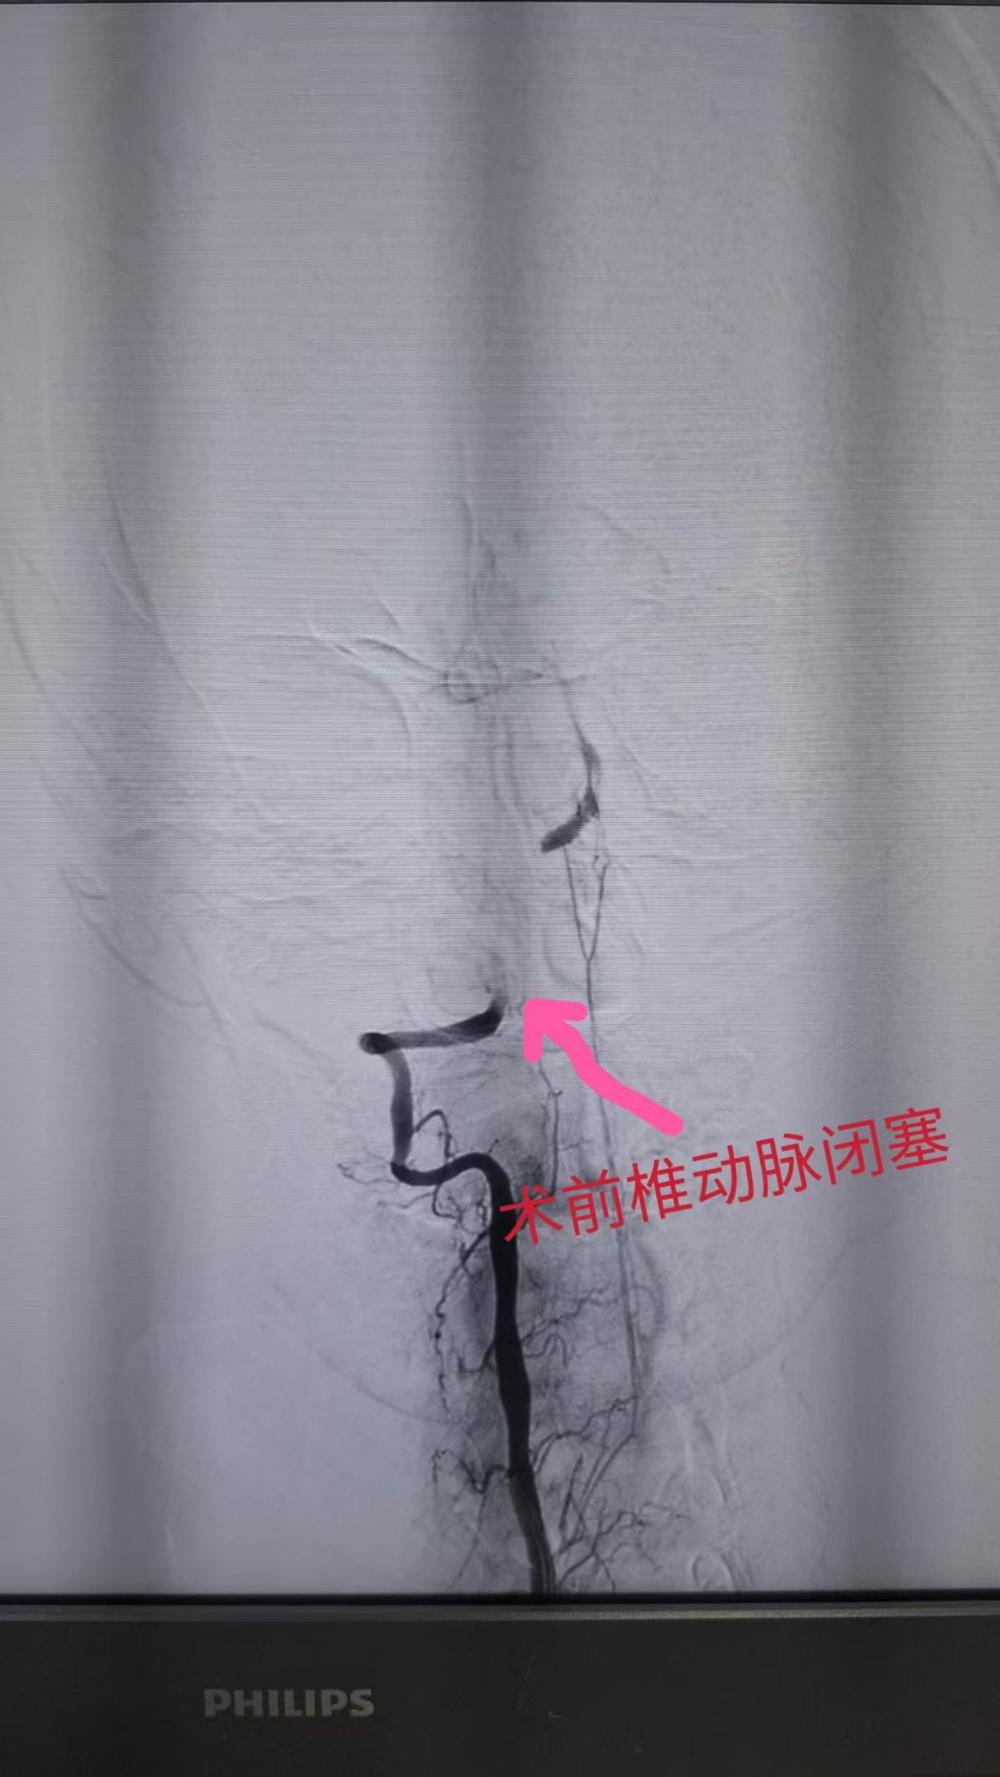

静脉溶栓治疗立即展开!与此同时,脑血管检查揭示了更危急的情况——钟先生双侧椎动脉闭塞,右椎优势。消息传来,所有人的心都揪紧了。

手术室里,胡华林主任带领神经内科介入团队快速制定方案,每一个动作都精准而迅速。介入取栓加椎动脉支架置入手术紧张进行,医护人员屏息凝神,目光紧盯着显示屏上血管的每一个变化。终于,通了!闭塞的椎动脉成功再通! 血流恢复的那一刻,不仅是血管的畅通,更是一个生命的重生。